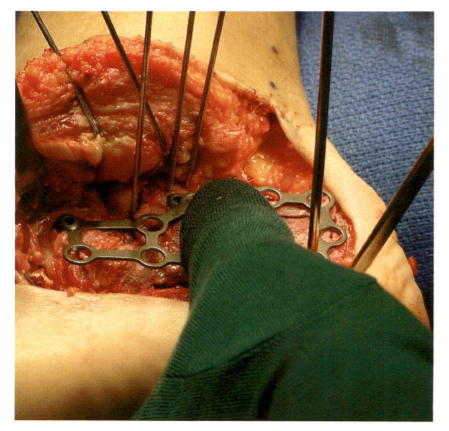

在跟骨外侧,需直接切至骨膜表面,将皮瓣全层掀开,避免损伤腓肠神经。皮瓣翻起后,采用克氏针固定于周围骨质,暴露跟骨外侧壁,同时避免损伤皮瓣内神经。

2. “不接触”技术牵开皮瓣“不接触”技术通常采用4枚1.6mm克氏针,分别固定在:

① 腓骨远端;牵引皮瓣近端;② 距骨颈;牵开肌腱与皮瓣中间部分;③ 骰骨;牵开肌腱远端部分;④ 距骨体;有助于暴露后关节面。弯曲克氏针使皮瓣回缩,在后续手术操作过程中,无需触及皮瓣。

3. 骨折复位与固定皮瓣掀开后暴露跟骨外侧壁,此时跟骨外侧壁可能阻挡骨折复位及骨折线的观察,将外侧壁骨块取出;